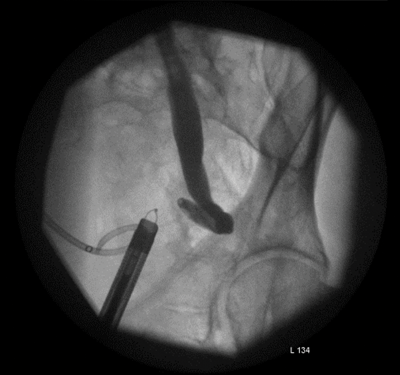

Figure 2.

The lower ureter was tortuous and of the ‘fish-hook’ type. A nephrostogram revealed a stricture at the vesicoureteric junction (VUJ) and incision of the VUJ using a Collins knife failed to demonstrate the lumen (Figure 2 and 3).